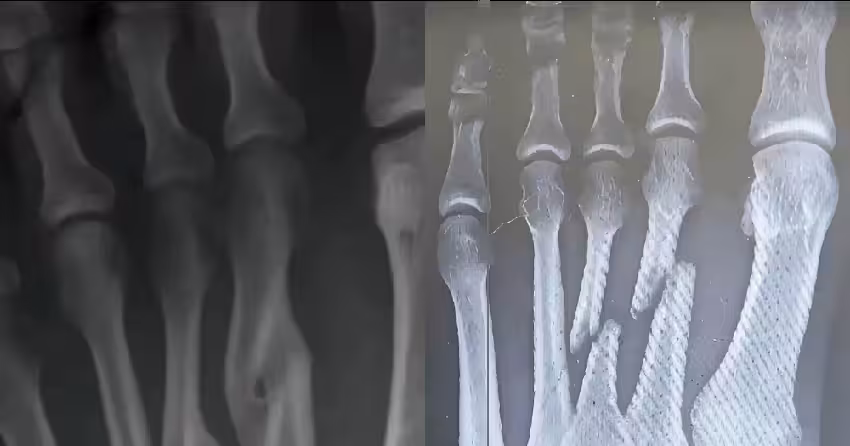

有網友分享類似經歷:小學同學接骨後長歪,不得不掰斷重接;有人感慨過去正骨打石膏的療法如今被鋼釘取代;也有醫學背景的網友指出,雖然自愈可能,但畸形癒合會影響功能,手術仍是首選。

李阿嬤的案例像一面鏡子,照見了現代醫學與傳統觀念的碰撞。

醫學發展讓我們更信賴技術,但人類身體的自愈能力,依然藏著未被完全理解的奧秘。

如今,李阿嬤已能慢慢行走,腳踝上的隆起成為這段經歷的印記。